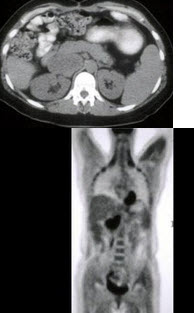

264、单项选择题

男,55岁,有结肠癌史,结合图像,最可能的诊断是()

A.肝转移

B.结肠癌复发

C.门静脉栓塞

D.十二指肠癌

E.以上都不是